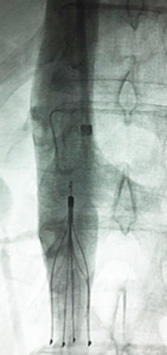

IVC Filter placed by Dr. Sheorain in the large Vein of body called Inferior Vena Cava aka IVC.

IVC filter Removal by Dr. Sheorain